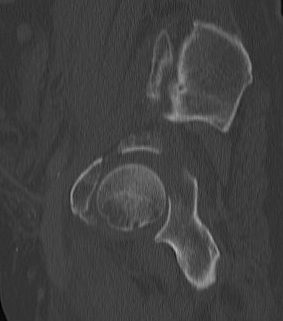

CT

Configuration

1-2 mm sections

CT reconstruction

- remove head to view acetabulum

- beware volume averaging

- used to guide surgery

Diagnose

Loose bodies

Femoral head fractures

Subtle subluxation

Articular steps

Roof arc measurement

A. Matta roof arc measurements

Describe location of fracture lines in relation to roof of acetabulum

- integrity of acetabular roof

- must be no hip subluxation

3 roof arc measurements

- AP, 2 Judet's views

- vertical line to centre of head

- line to where fracture enters joint

- the larger the arc, the further the fracture from the roof

- 10o - fracture in roof

- 900 - low fracture

Weight bearing dome is intact if angle > 45o on all 3 views